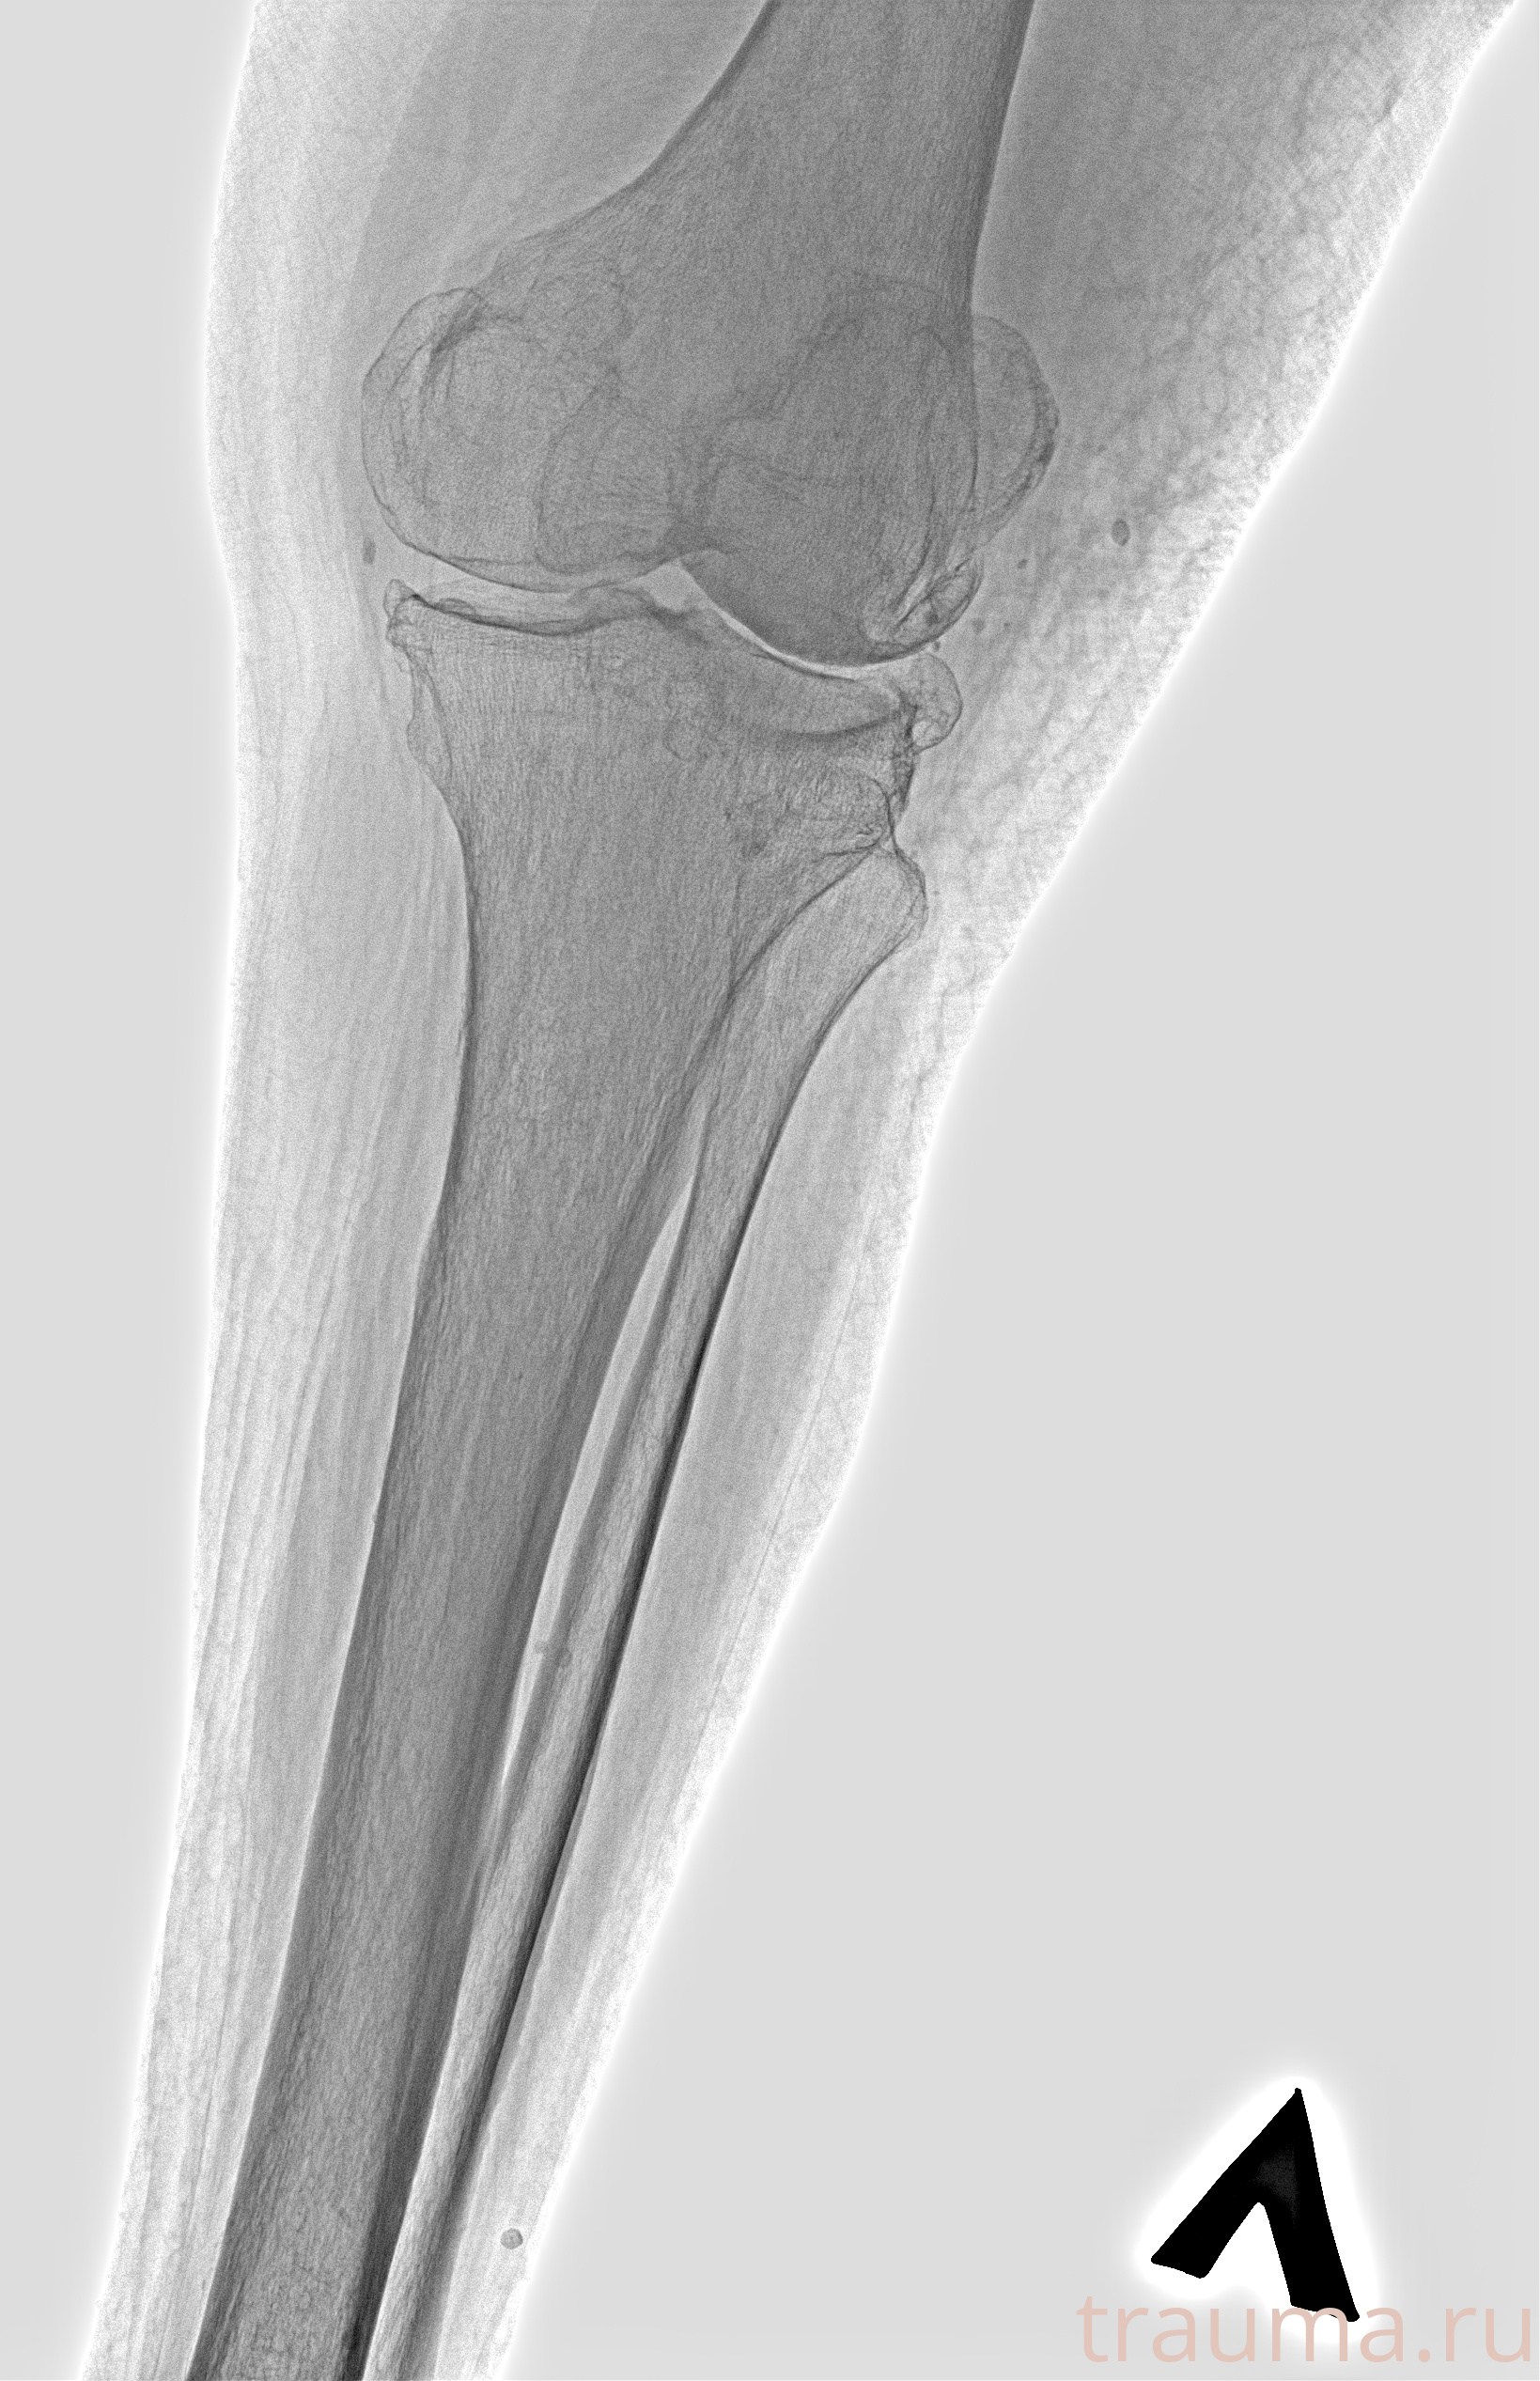

Рентген на дому: по вашему адресу приезжает врач-рентгенолог, травматолог-ортопед с мобильным рентгеновским аппаратом, проводит диагностику травмы или заболевания, делает необходимые рентгенограммы, дает рекомендации по дальнейшему лечению. Получить качественные снимки в домашних условиях возможно благодаря уникальной методике, разработанной МосРентген Центром для института  Склифосовского